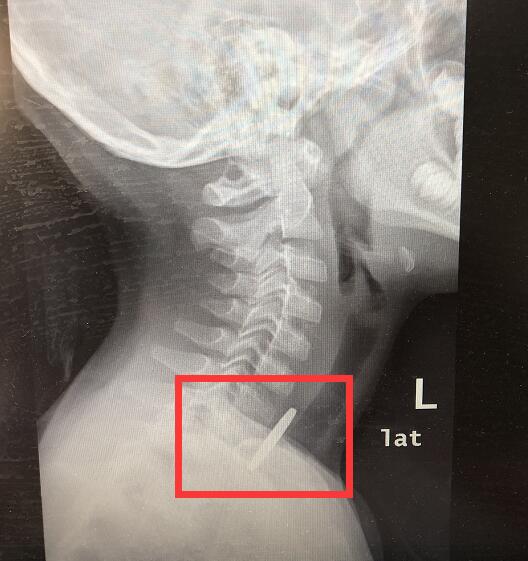

医生检查发现,一个圆形金属异物卡在了孩子的食管第一狭窄处,消化内科立即联合麻醉科为孩子准备施行异物取出术。

消化内科主任医师马春涛主要负责操作硬币夹取。据马春涛介绍,硬币卡在食管上端,需要及时取出,否则硬币压迫食管,可能会造成出血等。小孩子的食管壁薄、空间较窄,夹取硬币的过程中,稍有不慎,容易造成划伤食管或是硬币掉入气管的风险。还好夹取过程非常顺利,医生很快将异物取了出来,这个圆形的金属异物竟是一枚一元硬币。